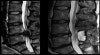

마미증후군의 영상 검사

MRI, CT, 척수조영술 검사에서 수막(thecal sac)이 심하게 눌려있는 소견을 보입니다.

MRI : 마미증후군(Cauda equina syndrome)